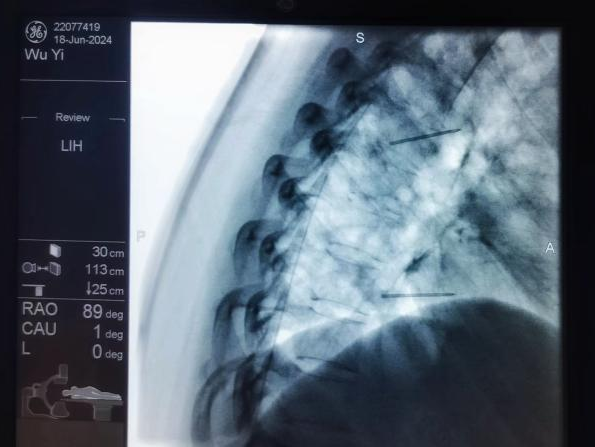

鞘内泵植入术:将药物输注导管植入鞘内,通过体外或体内泵持续输入镇痛药物,作用于中枢阿片受体,治疗癌痛及顽固性疼痛。

鞘内泵植入术